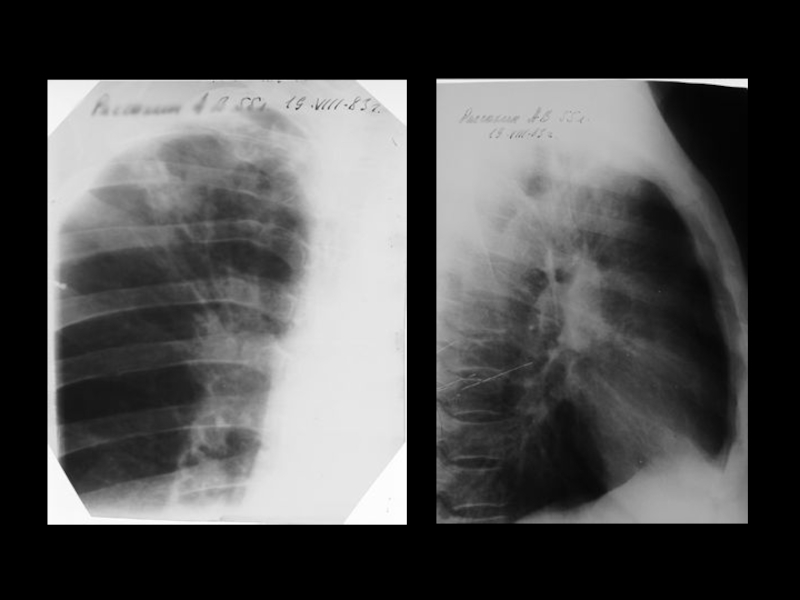

Центральный рак легкого

ЛУЧЕВАЯ ДИАГНОСТИКА РАКА ЛЕГКОГО